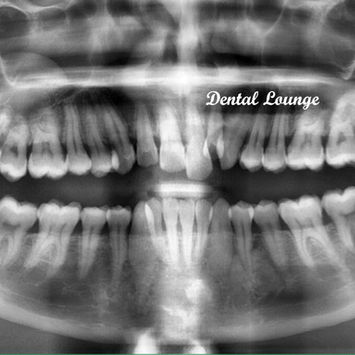

Surgical Removal of Impacted #38 with XAP of #37 and #28

Tooth #38: Completely buried in bone and impacted.

Tooth #37: Deep caries to the pulp with associated periapical lesion.

Tooth #28: Non-functional and supra-erupted.

Pre-operative CBCT taken.

Post-operative CBCT taken — no remnants noted.

Inferior dental nerve and maxillary sinus intact and not involved in surgery.